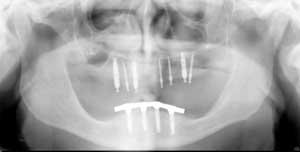

Each dentist has a level of diagnostic activity that he or she will accept. Some dentists have a complete diagnostic appointment, while others have superficial diagnostic appointments, obtaining only minimal information (Fig. 1 and Fig. 2). I have been involved as a consultant in numerous lawsuits in which some or all of the following negligent situations were evident: